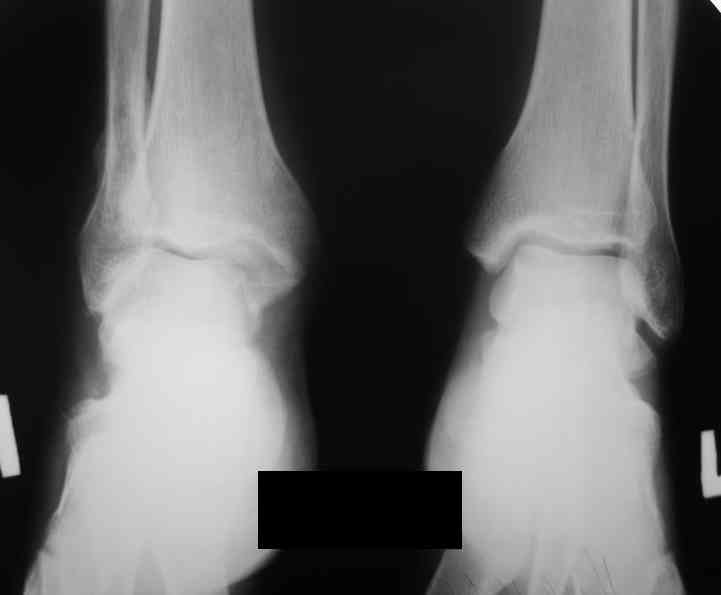

Уважаемые коллеги. Хотелось бы услышать ваше мнение по следующему случаю Обратился больной 23 года, травма 4 месяца назад - закрытый перелом наружной, внутренней лодыжки правой голени. Лечился консервативно, гипсовой иммобилизацией 8 недель, после снятия последней прошел курс восстановительного лечения. Беспокоят боли в области правого голеностопного сустава больше в проекции внутренней лодыжки, к вечеру. Отечность области сустава при физических нагрузках.Походка не изменена. Контуры правого голеностопного сустава сглажены. Имеется вальгусная установка правой пяточной кости. Объем движений в голеностопном суставе подошвенное / тыльное сгибание 50/0/80, безболезненные. Посоветуйте что делать в данной ситуации. Мне видится следующий вариант решения данной деформации: Восстановление нормальной анатомии голеностопного сустава - остеотомия малоберцовой кости и внутренней лодыжки, удалить все рубцы из области дистального межберцового синдесмоза, восстановить длину и устранить ротационное смещения наружной лодыжки.( встанет ли таранная кость на место?), фиксация наружной лодыжки пластиной, внутренней - винтами, дистального межберцового синдесмоза винтом. ЭОПом не располагаем. Что вы посоветуете? Где могут быть - технические трудности, <подводные камни>.

P.S. На боковой проекции таран выглядит несимпатично. Может быть изза качества снимка?